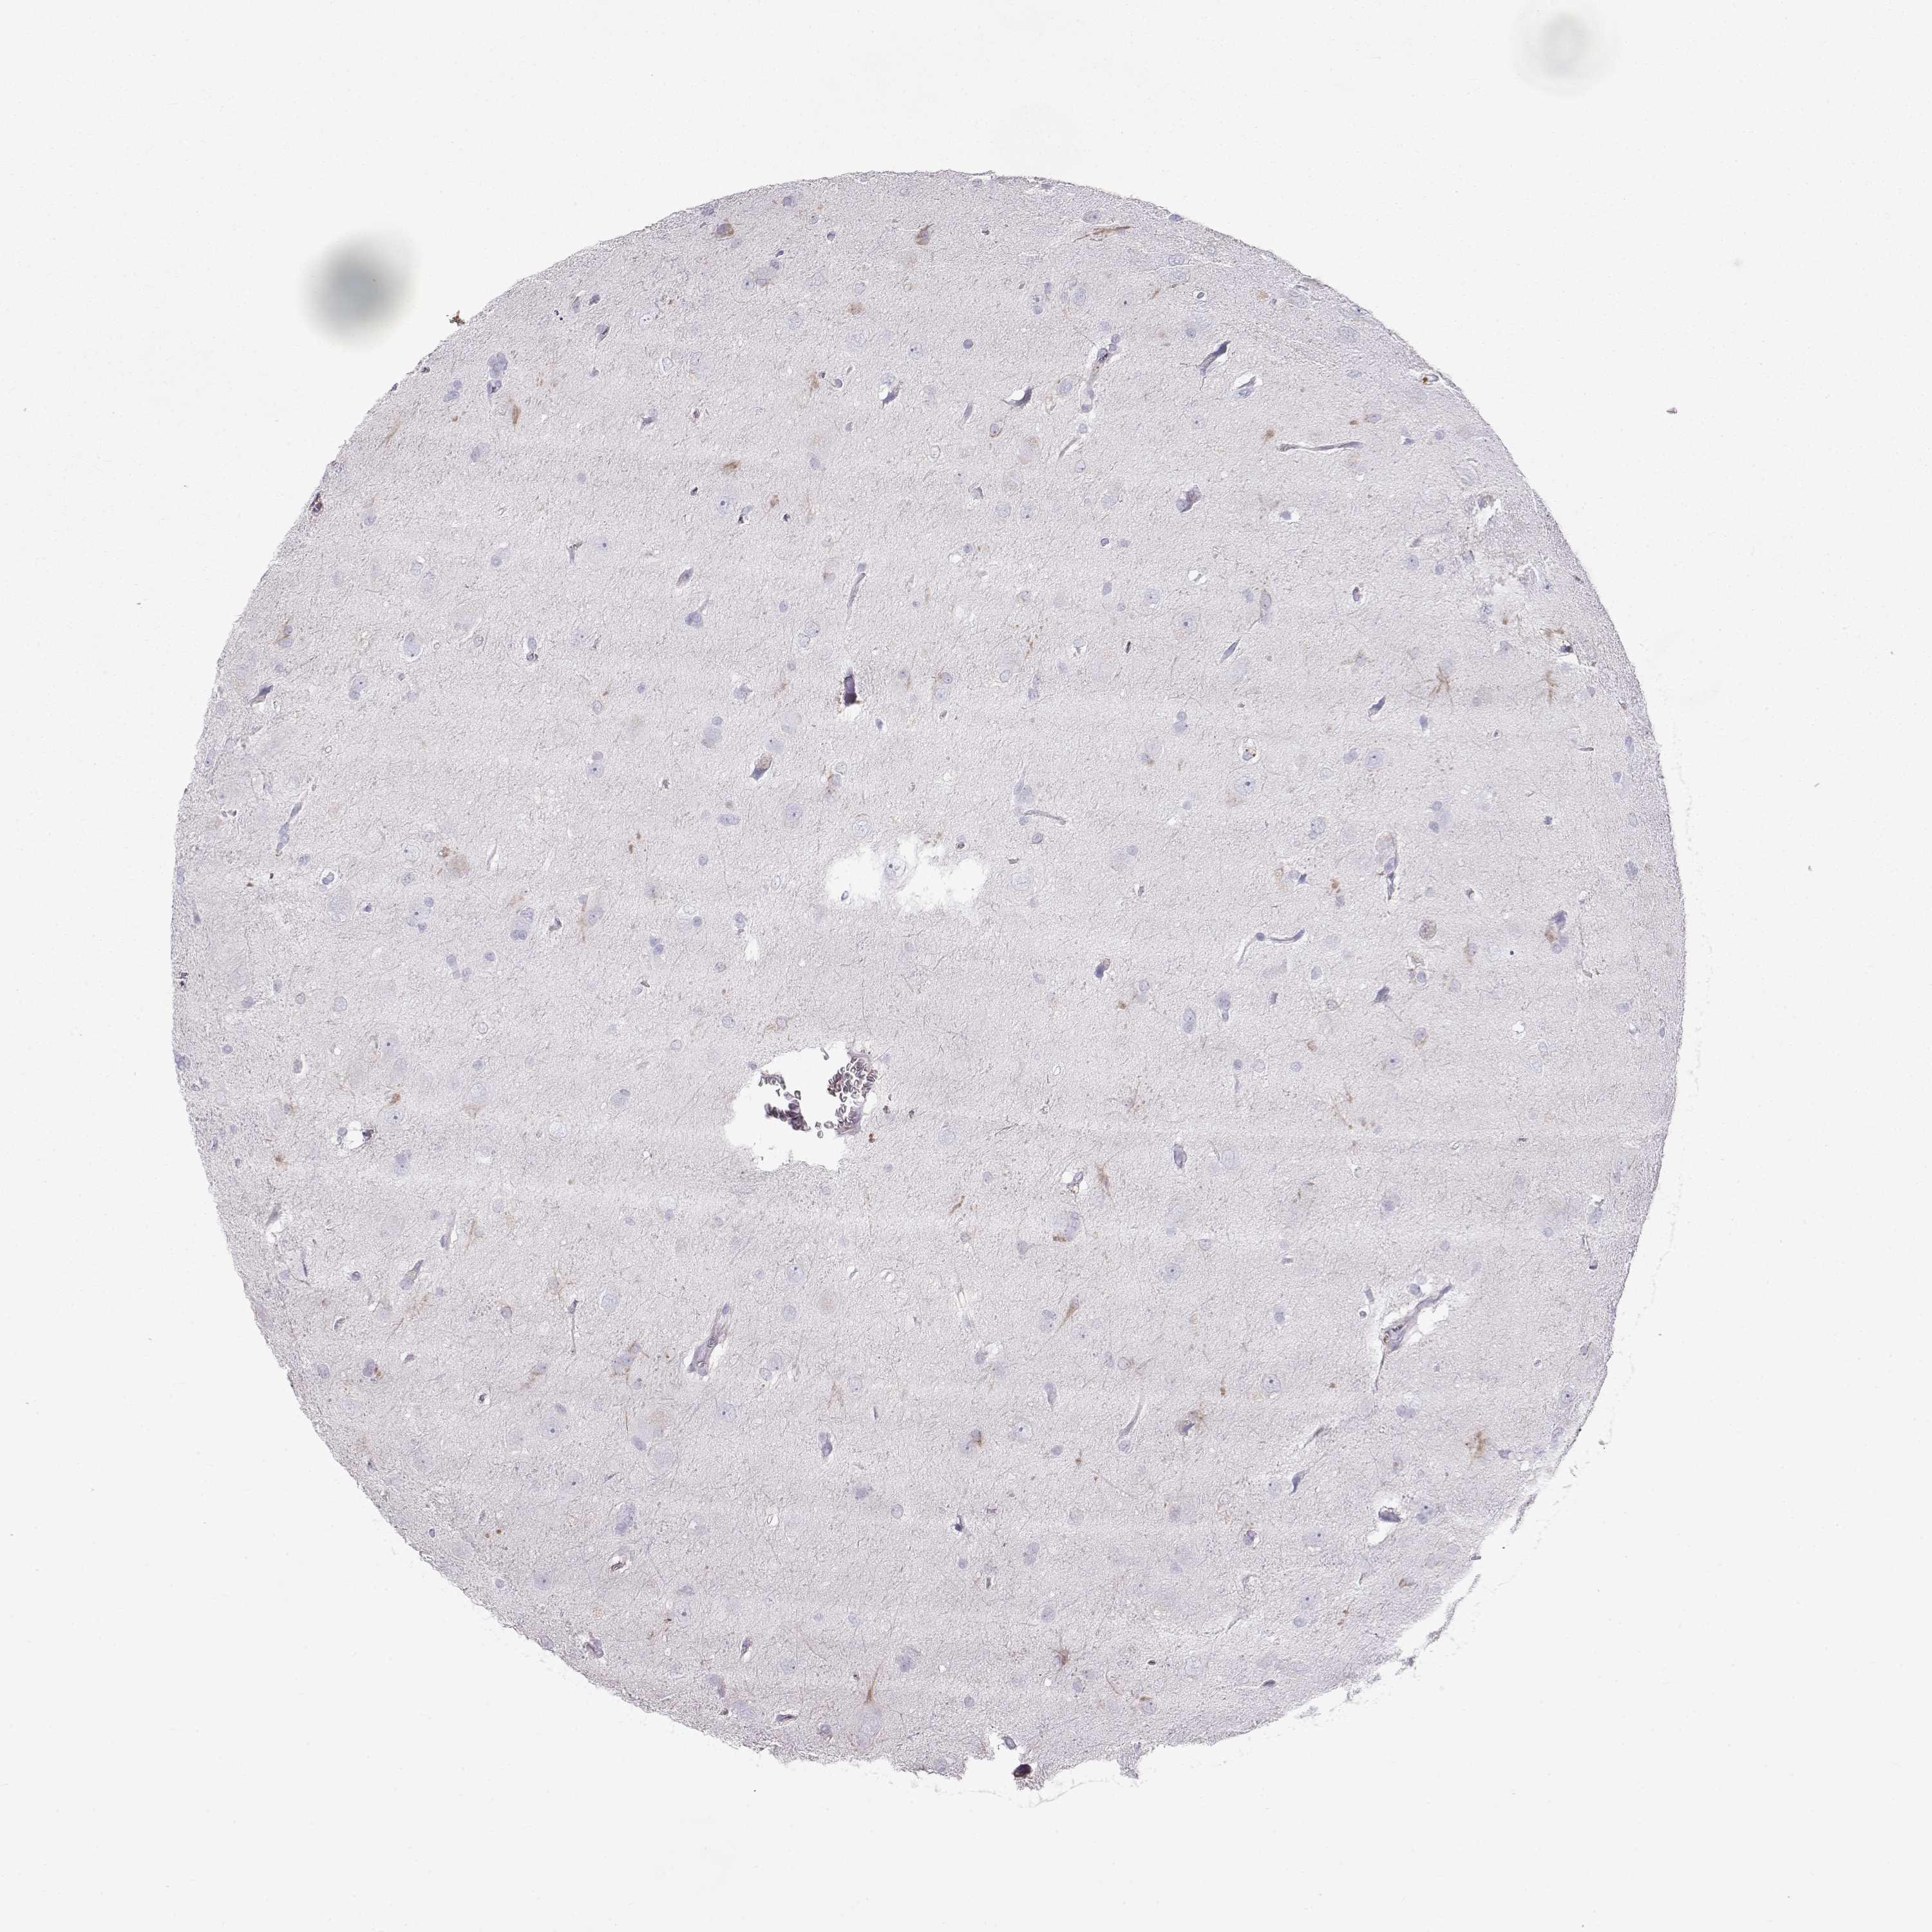

GLIOMA - Protein expressioni

A mouse-over function shows sample information and annotation data. Click on an image to view it in a full screen mode. Samples can be filtered based on level of antibody staining by selecting one or several of the following categories: high, medium, low and not detected. The assay and annotation is described here.

Note that samples used for immunohistochemistry by the Human Protein Atlas do not correspond to samples in the TCGA dataset.

Antibody stainingi

Antibody staining in the annotated cell types in the current human tissue is reported as not detected, low, medium, or high, based on conventional immunohistochemistry profiling in selected tissues. This score is based on the combination of the staining intensity and fraction of stained cells.

Each image is clickable and will lead to virtual microscopy that enables deeper exploration of all samples and also displays staining intensity scores, fraction scores and subcellular localization as well as patient and tissue information for each sample.

Antibody HPA062736

Staining

High

Medium

Low

Not detected

Intensity

Strong

Moderate

Weak

Negative

Quantity

>75%

75%-25%

<25%

None

Location

Nuclear

Cytoplasmic/membranous

Cytoplasmic/membranous,nuclear

Glioma, malignant, Low grade

Glioma, malignant, High grade